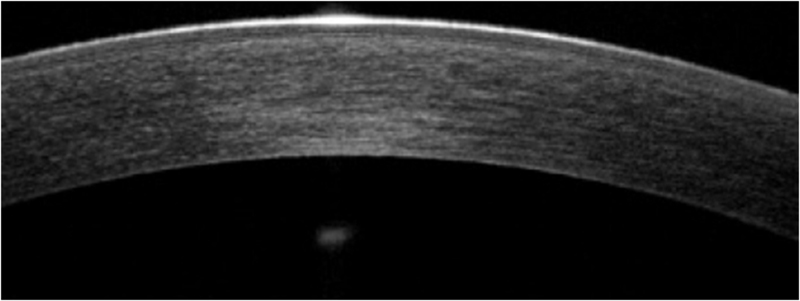

Y finalmente podemos hablar de la última técnica, la más complicada, por el hecho de trabajar con un injerto extrafino, solo se trasplanta la MD y el endotelio, estamos hablando de la DMEK. Vemos unos ejemplos, como la

Figura 12, es una OCT de la parte central de la córnea, prácticamente indistinguible de una cornea sana y en la

Figura 12. DMEK zona central.